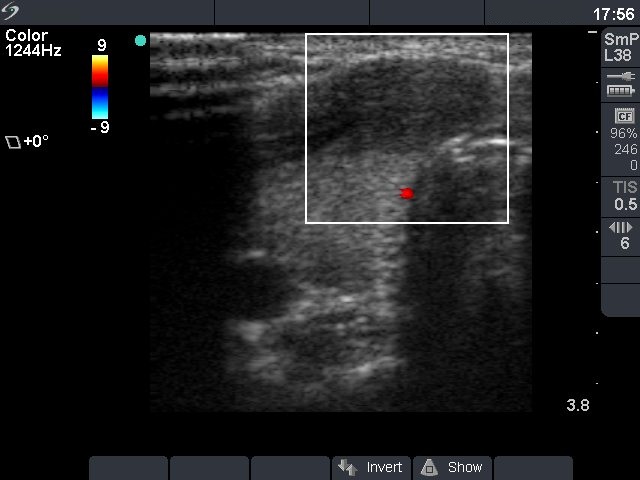

Ultrasonography: there was a hypoechogenic nodule in the ventromedial part of the left lobe. The nodule had increased in size from 8x5x9 mm to 16x14x19 mm over three years.